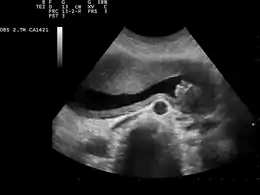

السائل الأمنيوتي أو الأمينوسي (بالإنجليزية: Amniotic fluid) هو سائل غذائي ويُوفر الحماية للجنين يُوجد داخل الكيس الأمنيوتي في رحم المرأة.[1][2][3]

ينمو الكيس الأمنيوتي ويبدأ بالامتلاء، ولا سيما بالسائل بعد أسبوعين تقريبا من التلقيح. بعد 10 أسابيع في وقت لاحق يحتوي السائل على البروتينات و الكربوهيدرات، و الدهون، و الدهون الفوسفاتية و سماد اليوريا و الشوارد، والتي تساعد في نمو الجنين. ويستمر إنتاج السائل الذي يحيط بالجنين عن طريق السوائل التي تخرج من جلد الجنين حتى الإسبوع 14 من الحمل حتى النقطة التي يبدأ فيها الجلد بالتقرن. خلال الأسابيع 8-11، يبدأ الجنين في ابتلاع والتبول فيه، وهذا هو السبب في السائل الأمنيوتي يحتوي على البول في مراحل لاحقة من الحمل. يزداد حجم السائل الأمنيوتي بنمو الجنين. تصل كمية السائل الأمنيوتي أعظم ما يكون عند الاسبوع 34 من عمر الحمل حيت تكون حوالي 800 مليلتر. ثم تنخفض كمية السائل إلى ما يقرب من 600 مليلتر في الأسبوع 40 من الحمل، والذي يكون عادة عند ولادة الطفل. يخرج السائل الأمنيوتي عندما تتمزق السلى. ومن المعروف أن هذا يحدث أثناء المخاض، كما هو معروف " تمزق الأغشية العفوي " (تمزق السلى). إذا تمزق قبل المخاض، يشار إليها بأنها "تمزق الأغشية قبل الأوان") غالبية السائل يبقى داخل الرحم حتى ولادة الطفل . ويمكن أيضا تمزيق الغشاء اصطناعيا، أي تمزيق الكيس الأمنيوتي، ويؤدي لخروج السائل إذا لم تتمزق السلى عفويا .

في كل زيارة ما قبل الولادة، وينبغي على طبيب التوليد / أمراض النساء أو القابلة قياس ارتفاع قاع الرحم بشريط قياس. ومن المهم أن يكون قياس ارتفاع قاع الرحم وتسجيلها بشكل صحيح لضمان نمو الجنين السليم وتنمية متزايدة من السائل الأمنيوتي. وينبغي على طبيب التوليد / أمراض النساء أيضا استعمال الموجات فوق الصوتية بشكل روتيني للمرضى، هذا الإجراء سيعطي أيضا مؤشرا على نمو الجنين السليم وتنمية السائل الأمنيوتي. يمكن أن يكون سبب قلة السائل Oligohydramnios عن طريق العدوى، أو اختلال وظيفي في الكلى أو تشوه (حيث أن كثير من حجم السائل الأمنيوتي يكون من البول كما أشرنا سابقا)، وإجراءات مثل خزعة المشيمة، والتمزق المبكر للأغشية قبل الأوان (PPROM). يمكن في بعض الأحيان أن تعالج القلة Oligohydramnios بالراحة في الفراش، والماء عن طريق الفم عن طريق الوريد والمضادات الحيوية والمنشطات، ومن المهم أيضا أن تبقي الطفل دافئا. كثرة السلى هو أحد عوامل الخطر المهيئة لتدلي الحبل، وأحيانا من الآثار الجانبية للحمل بجنبن كبير الحجم. ويرتبط كثرة السلى مع رتق المريء. ويتم إنتاج السائل الأمنيوتي في المقام الأول من قبل الأم حتى 16 أسبوعا من الحمل.

بزل السَّلَى : أخذ عينة من السائل الموجود في الكيس السَّلوي (الأمنيوسي)، وهو السائل الذي يسبح فيه الجنين في بطن أمه. غالبية هذا السائل يتكون من بول الطفل ويحتوي على خلايا من أمنيوسية بالإضافة إلى خلايا الجلد الميتة. وتُجرى هذه العملية بعد الإسبوع الخامس عشر من الحمل، وذلك بإدخال إبرة في البطن للوصول إلى رحم المرأة. ويمكن عزل الخلايا المتواجدة في السائل السلي واستخدامها لتعيين جنس الجنين، وعدد المورثات (الكروموسومات) ودراسة الجينات بالكامل.